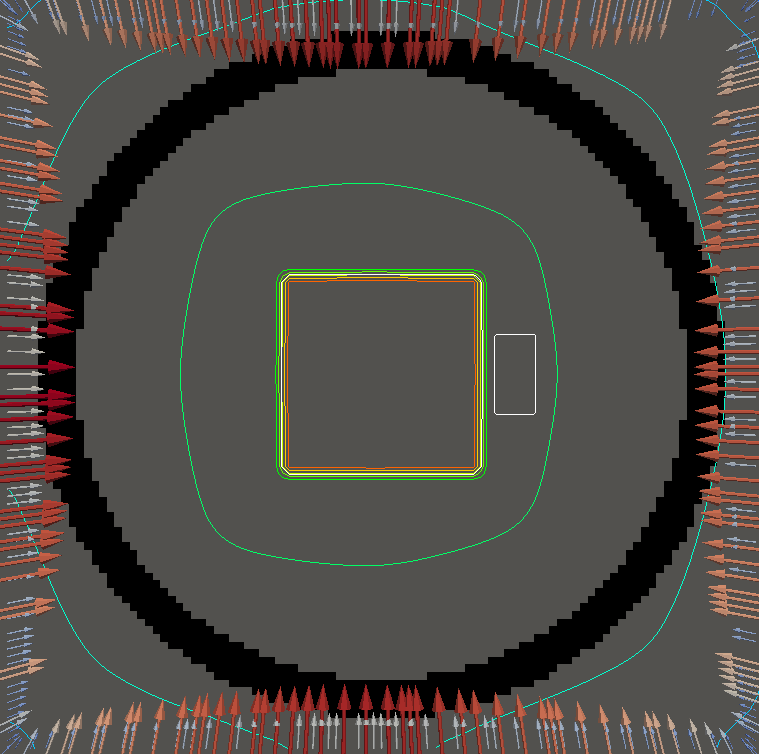

For testing, we use three tumor/risk region regions similar to those in [13]. Specifically, we define the regions in Table 3 and are shown in Figure 1; the void region is shown in black and the tumor and risk regions are traced in white. In the basic target case, seen in Figure 1(a), the tumor region is a box, as is the risk region. The second, intermediate target case, seen in Figure 1(b), involves an L-shaped tumor around a box-shaped risk region. Finally, the complex target case in Figure 1(c) involves a C-shaped tumor around a risk region.

Figure 2 shows the optimal boundary source term for both and The vectors shown on the boundary are the time-integrated values of normalized and then scaled by In Figures 2(a), 2(c), and 2(e) (corresponding to ), the isolines are spaced at intervals of the maximum of the desired dose (here, 5). In the intermediate and tracking cases, we see that relatively low dose levels are attained, primarily due to the high penalty to any dose deposited in the risk region. In Figures 2(b), 2(d), and 2(f)(corresponding to ), the isolines are spaced at intervals of of cells killed. Here a high proportion of the tumor cells are killed (in each case ) while in the Intermediate and Basic cases, the tumor has at least survival; in the Complex case, the risk region has survival.